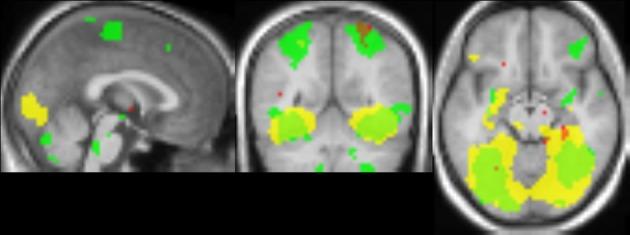

Using textures mapped onto virtual nonsense objects, it has recently been shown that early visual cortex plays an important role in processing material properties. Here, we examined brain activation to photographs of materials, consisting of wood, stone, metal and fabric surfaces. These photographs were close-ups in the sense that the materials filled the image. In the first experiment, observers categorized the material in each image (i.e., wood, stone, metal, or fabric), while in an fMRI-scanner. We predicted the assigned material category using the obtained voxel patterns using a linear classifier. Region-of-interest and whole-brain analyses demonstrated material coding in the early visual regions, with lower accuracies for more anterior regions. There was little evidence for material coding in other brain regions. In the second experiment, we used an adaptation paradigm to reveal additional brain areas involved in the perception of material categories. Participants viewed images of wood, stone, metal, and fabric, presented in blocks with images of either different material categories (no adaptation) or images of different samples from the same material category (material adaptation). To measure baseline activation, blocks with the same material sample were presented (baseline adaptation). Material adaptation effects were found mainly in the parahippocampal gyrus, in agreement with fMRI-studies of texture perception. Our findings suggest that the parahippocampal gyrus, early visual cortex, and possibly the supramarginal gyrus are involved in the perception of material categories, but in different ways. The different outcomes from the two studies are likely due to inherent differences between the two paradigms. A third experiment suggested, based on anatomical overlap between activations, that spatial frequency information is important for within-category material discrimination.

利用映射到虚拟无意义物体的纹理,最近已经证明早期视觉皮层在处理材料属性方面起着重要作用。在这里,我们研究了对材料照片的大脑激活,这些材料包括木材、石材、金属和织物表面。这些照片是特写镜头,因为材料充满了图像。在第一个实验中,观察者在 fMRI 扫描仪中对每张图像中的材料(即木材、石材、金属或织物)进行分类。我们使用获得的体素模式使用线性分类器预测分配的材料类别。感兴趣区域和全脑分析表明,早期视觉区域存在材料编码,前部区域的准确性较低。在其他大脑区域几乎没有证据表明存在材料编码。在第二个实验中,我们使用适应范式来揭示参与感知材料类别的其他大脑区域。参与者观看木材、石材、金属和织物的图像,以块的形式呈现,块中包含不同的材料类别(无适应)或来自同一材料类别的不同样本的图像(材料适应)。为了测量基线激活,呈现具有相同材料样本的块(基线适应)。材料适应效应主要出现在旁海马回中,与纹理感知的 fMRI 研究一致。我们的研究结果表明,旁海马回、早期视觉皮层以及可能的缘上回参与了材料类别的感知,但方式不同。这两个研究的不同结果可能是由于两个范式之间的固有差异造成的。第三个实验基于激活之间的解剖重叠表明,空间频率信息对于类别内的材料辨别很重要。